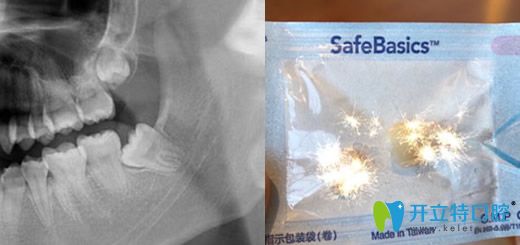

3、拔智齒

地點:口腔朝陽北路    醫(yī)生:趙曉嵐

<!--<i data=20240703-sp></i>-->口腔朝陽北路拔智齒

顧客點評:說實話,為了正畸拔智齒真是使用了我所有的勇氣,差點讓我決定不做正畸了,后來還是硬著頭皮來啦,真的拔了感覺還好吧,術(shù)后被叮囑了好多注意事項,服務(wù)非常贊,值得推薦。